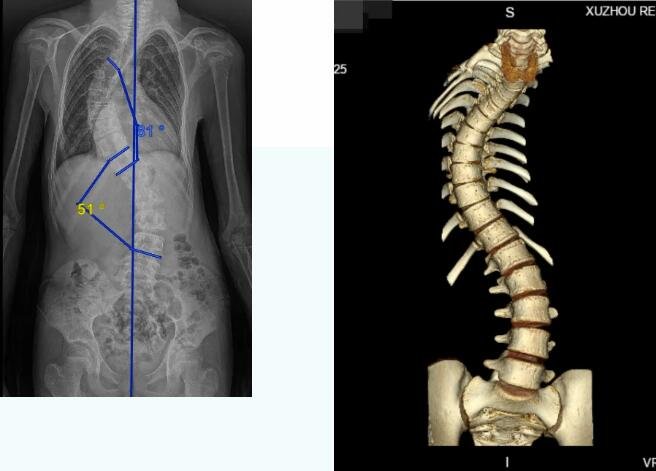

小俊脊柱现呈S型,尤其胸腰段扭曲最严重,侧弯的最大度数已达81度,驼背也51度,心、肺等重要脏器均收受到了不同程度的压迫。

小俊脊柱影像学检查

小俊所患的特发性脊柱侧弯是一种复杂的三维畸形,不仅存在冠状面的侧向弯曲,还伴有椎体旋转和矢状面畸形,手术难度、风险和复杂程度均高于普通脊柱侧弯手术。